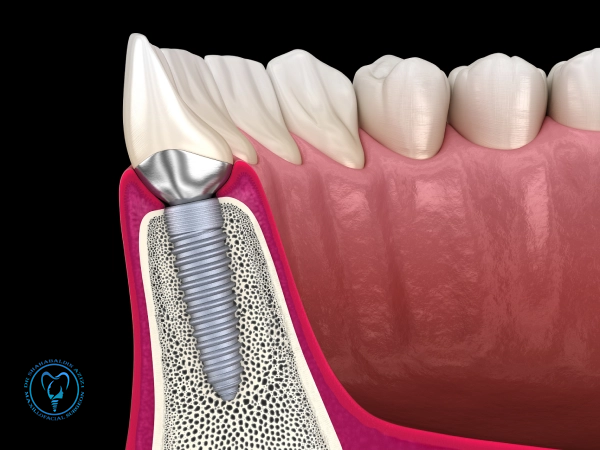

ایمپلنت طلا: راهنمای کامل، مزایا، معایب و هزینهها ایمپلنت طلا، یکی از گزینههای خاص، لوکس و بادوام در دندانپزشکی زیبایی است که هم جنبه درمانی دارد و هم میتواند نشاندهنده سبک و سلیقه فرد باشد. در این مقاله به بررسی همهجانبه این نوع ایمپلنت میپردازیم. ایمپلنت طلا چیست؟ ایمپلنت طلا نوعی جایگزین دندان است که…